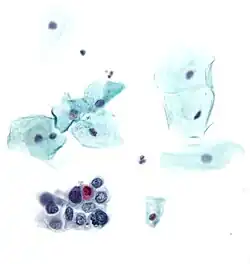

LSIL: low-grade squamous intraepithelial lesion

.png)

A low-grade squamous intraepithelial lesion (LSIL or LGSIL) indicates possible cervical dysplasia. LSIL usually indicates mild dysplasia (CIN 1), more than likely caused by a human papillomavirus infection. It is usually diagnosed following a Pap smear.

CIN 1 is the most common and most benign form of cervical intraepithelial neoplasia and usually resolves spontaneously within two years. Because of this, LSIL results can be managed with a simple "watch and wait" philosophy. However, because there is a 12–16% chance of progression to more severe dysplasia, the physician may want to follow the results more aggressively by performing a colposcopy with biopsy.[7] If the dysplasia progresses, treatment may be necessary. Treatment involves removal of the affected tissue, which can be accomplished by LEEP, cryosurgery, cone biopsy, or laser ablation.